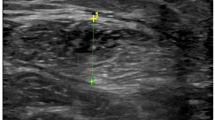

Measurement of muscle mass is paramount in the screening and diagnosis of sarcopenia. Besides muscle quantity however, also quality assessment is important. Ultrasonography (US) has the advantage over dual-energy X-ray absorptiometry (DEXA) and bio-impedance analysis (BIA) to give both quantitative and qualitative information on muscle. However, before its use in clinical practice, several methodological aspects still need to be addressed. Both standardization in measurement techniques and the availability of reference values are currently lacking. This review aims to provide an evidence-based standardization of assessing appendicular muscle with the use of US.

Through this process, five items of muscle assessment were identified in the evaluated articles: thickness, cross-sectional area, echogenicity, fascicle length and pennation angle. Different techniques for measurement and location of measurement used were noted, as also the different muscles in which this was evaluated. Then, a translation for a clinical setting in a standardized way was proposed.

The results of this review provide thus an evidence base for an ultrasound protocol in the assessment of skeletal muscle. This standardization of measurements is the first step in creating conditions to further test the applicability of US for use on a large scale as a routine assessment and follow-up tool for appendicular muscle.